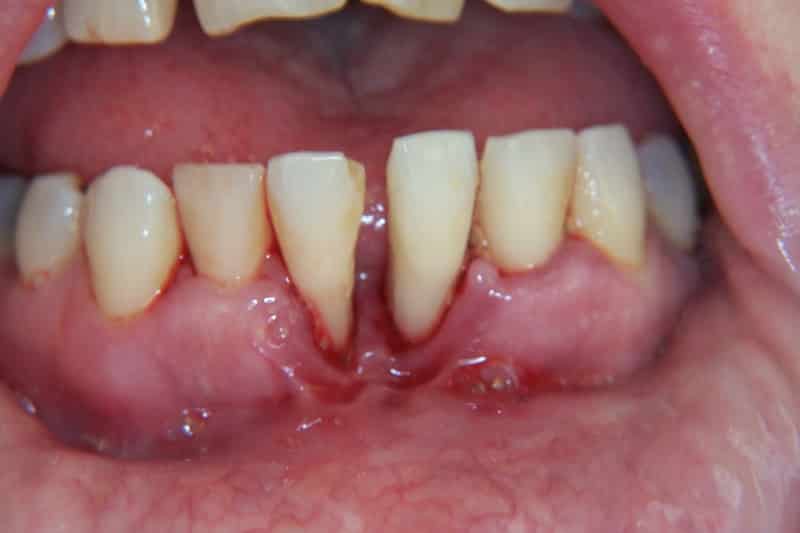

- Вторая стадия. Пародонтоз вызывает значительную рецессию дёсен и оголение зубных корней до трети их длины, зубы начинают сильнее расшатываться, выбиваясь из зубного ряда. Могут появляться скопления гноя и крови, слизистая меняет цвет и начинает чаще кровоточить.

- Третья стадия. Рецессия обнажает корни зубов на половину их длины, которые продолжают покрываться зубным камнем. Пародонтальный карман углубляется, и при контакте из дёсен появляются гнойные выделения. Зубы начинают свободно шататься в любом направлении, рентген показывает значительную атрофию альвеолярных отростков.

Пародонтоз — это заболевание, которое характеризуется прогрессирующим разрушением тканей, окружающих зубы. Врачи отмечают, что на начальных стадиях пародонтоз может проявляться незначительными симптомами, такими как покраснение и отечность десен. Однако по мере развития болезни наблюдаются более серьезные изменения. На фотографиях, иллюстрирующих это заболевание, можно увидеть отступление десен, образование карманов между зубами и деснами, а также появление зубного камня. Врачам важно подчеркнуть, что своевременная диагностика и лечение могут значительно замедлить прогрессирование пародонтоза и сохранить здоровье зубов. Визуальные признаки заболевания могут варьироваться, но в любом случае требуют внимания специалиста для предотвращения серьезных осложнений.

| Кровоточивость десен | Десны кровоточат при чистке зубов, приеме твердой пищи или даже спонтанно. | [Изображение кровоточащих десен] |